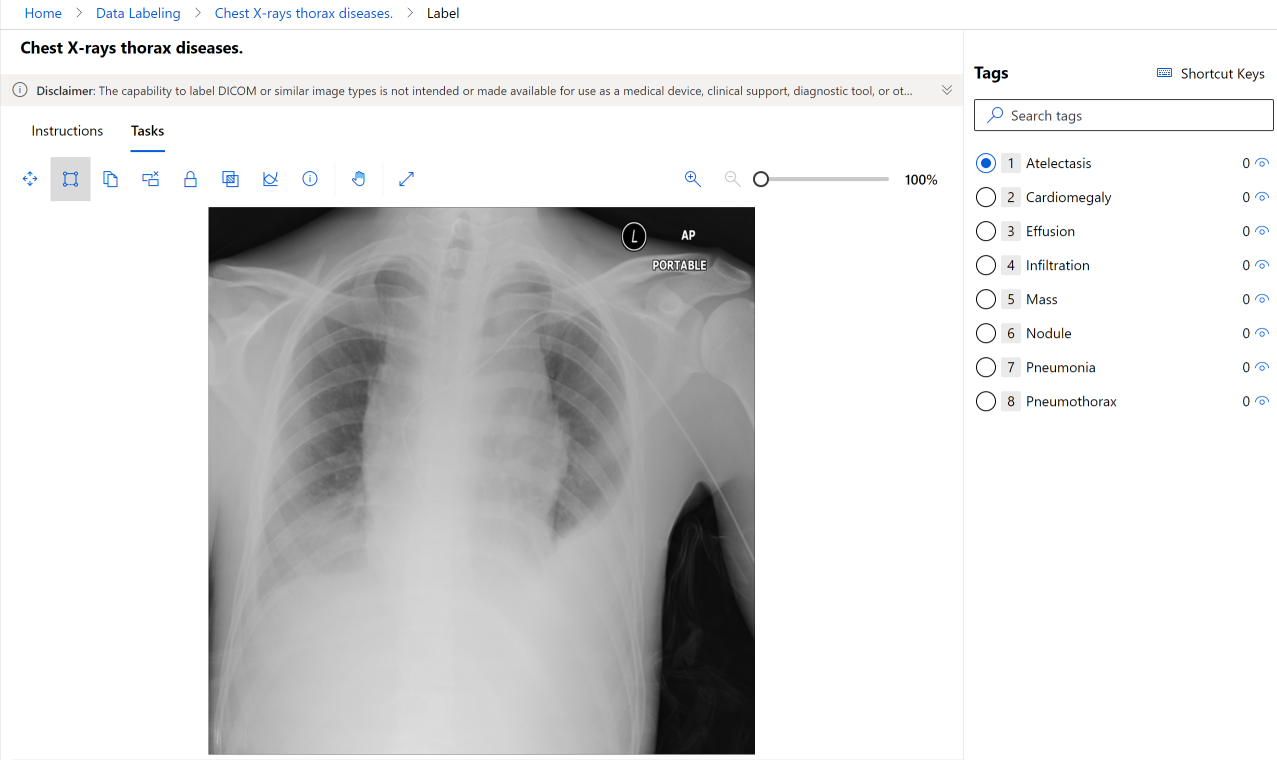

医学图像任务

重要

为 DICOM 或类似图像类型设置标签的功能不应用于或不可供用于医疗设备、临床支持、诊断工具或者其他旨在用于诊断、治愈、缓解、治疗或预防疾病或其他健康问题的技术,Microsoft 不授予将此功能用于此类目的的任何许可或权利。 此功能不旨在代替专业人员医疗建议或保健意见、诊断、治疗或医疗保健专业人员临床判断而实施或部署,并且不应用作此用途。 客户只负责对 DICOM 或类似图像类型使用数据标签。

图像项目支持用于 X 光文件图像的 DICOM 图像格式,如以下屏幕截图所示:

虽然你在标记医学图像时使用的工具与其他图像相同,你也可以使用另一个工具来处理 DICOM 图像,如以下屏幕截图所示:

选择“窗口和级别”工具,以更改图像的强度。 此工具只可用于 DICOM 图像。